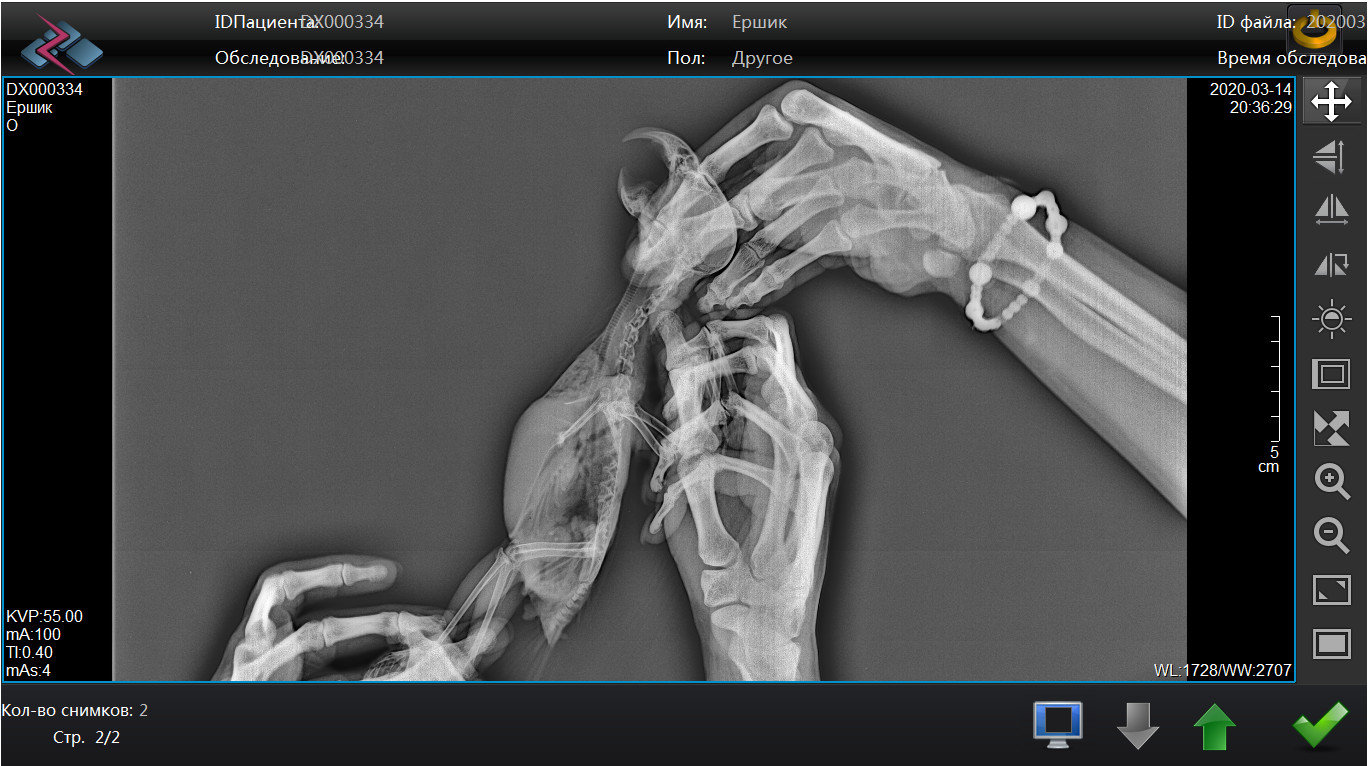

Pipka Опубликовано 18 апреля, 2020 Автор #73 Опубликовано 18 апреля, 2020 11.04.2020 в 21:10, Мария_К сказал: @Pipkaв надежде на хорошие новости от вас. @Мария_К , И ура!!!! Они таки хорошие!!!!!!! Люди, народ, поздравьте нас с Ёршиком!!!!!!! Мы поправились!!!! Не надо больше уколов, мерзких гадких заворачиваний в полотенце и принудительных выпаиваний горьким лекарством. МЫ ЗДОРОВЕНЬКИЕ!!!!! Посмотрите какой у нас чистенький и светленький рентгенччииккккк!!!!!!! Никаких затемнений, никаких гранулем или остаточных швов на легких. В сравнении с тем что было - день и ночь. Даже мне стало понятно и видно все. Мы поправились. По клинической картине: чихов нет, хрипов-сипов нет, нос чистейший, морду не трет, головой не дергает. Чуть позже выложу ввидео с ним. Пока вот рентген. Господи, как же я счастлива!!!!! Про липому все также. Без изменений. Но нам сказали что это фигня. Если будет правильно питаться и двигаться то больше чем есть не вырастет...

Pipka Опубликовано 18 апреля, 2020 Автор #74 Опубликовано 18 апреля, 2020 Извините, полосы - это мерцание на компе от телефона. Мне так не терпелось, что я прямо с компа на телефон щелкнула. а так ответ на диске, а у меня дома дисковода нема.

Pipka Опубликовано 18 апреля, 2020 Автор #75 Опубликовано 18 апреля, 2020 Мне все-таки кажется что главным в лечении был вариконазол. хотяя... может и байтрил и ингаляции свое дело сделали. Кстати, ингаляции я ему решила пока не отменять. пусть утром и вечером дышит хорошими парами полезными. Вместо курева того страшного. И элькар конечно в поилке. карсил и костная мука в кормушке. На этом пока остановимся..